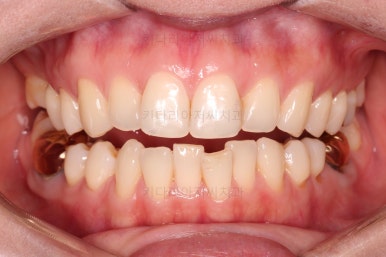

부산치아교정비용 전후 비교해 볼게요.

치료기간은 임플란트의 안정성 때문에 길어지긴 했으나 사실상 내원횟수는 그리 많지 않으셨고, 교정장치가 눈에 보이는 기간은 7개월정도 밖에 안되었기 때문에 크게 문제되지는 않았던 것 같습니다.

여러 가지가 다 잘 마무리 되었습니다.

이상 아래 앞니 부분교정 및 임플란트를 위한 어금니 부분교정 이후 임플란트까지 완성한 치료사례였고 부산치아교정비용과 가격도 대략 알아보는 시간이었습니다.